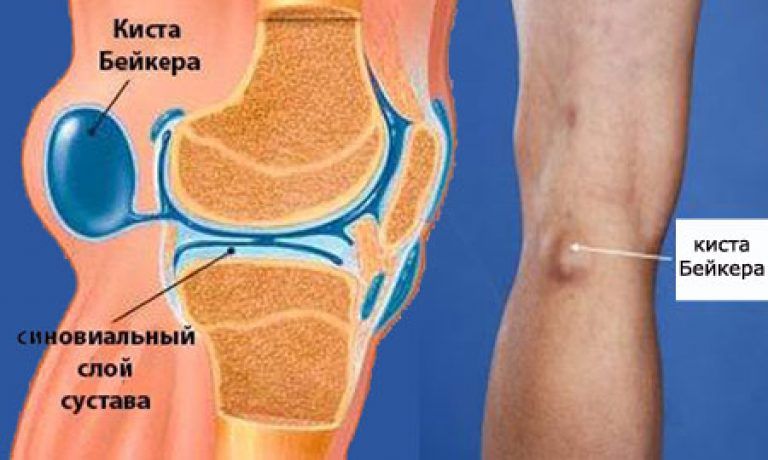

Заболевания и медицинские снимки: Жидкость в коленной чашечке